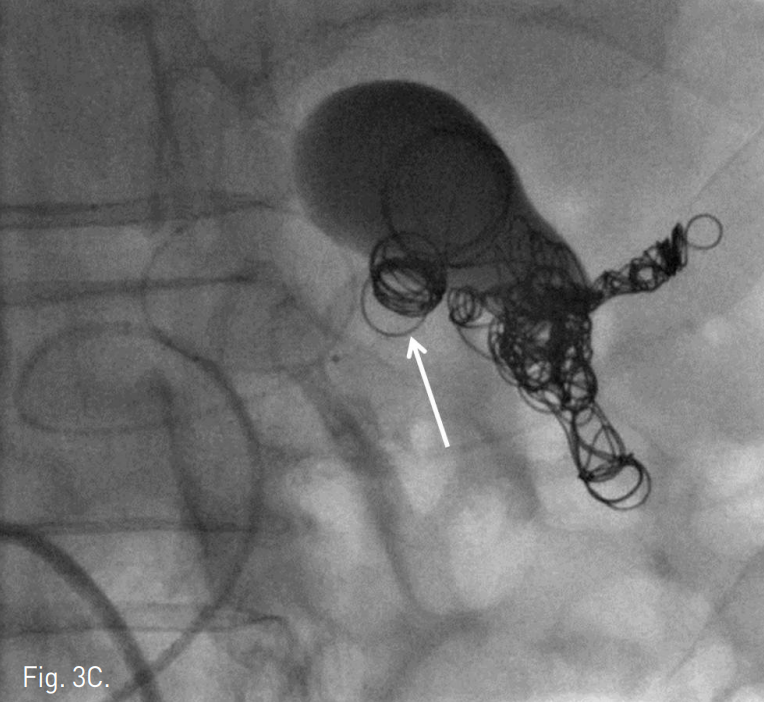

Fig. 3

Radiographs obtained during embolization. One of distal branch of splenic artery was embolized with IDC coils (arrow in A). The distal neck of aneurysm was embolized by multiple IDC coils (arrow in B), which was anchored to the small distal branch of splenic artery. Further embolization of proximal neck and part of aneurysmal sac was done (arrow in C).